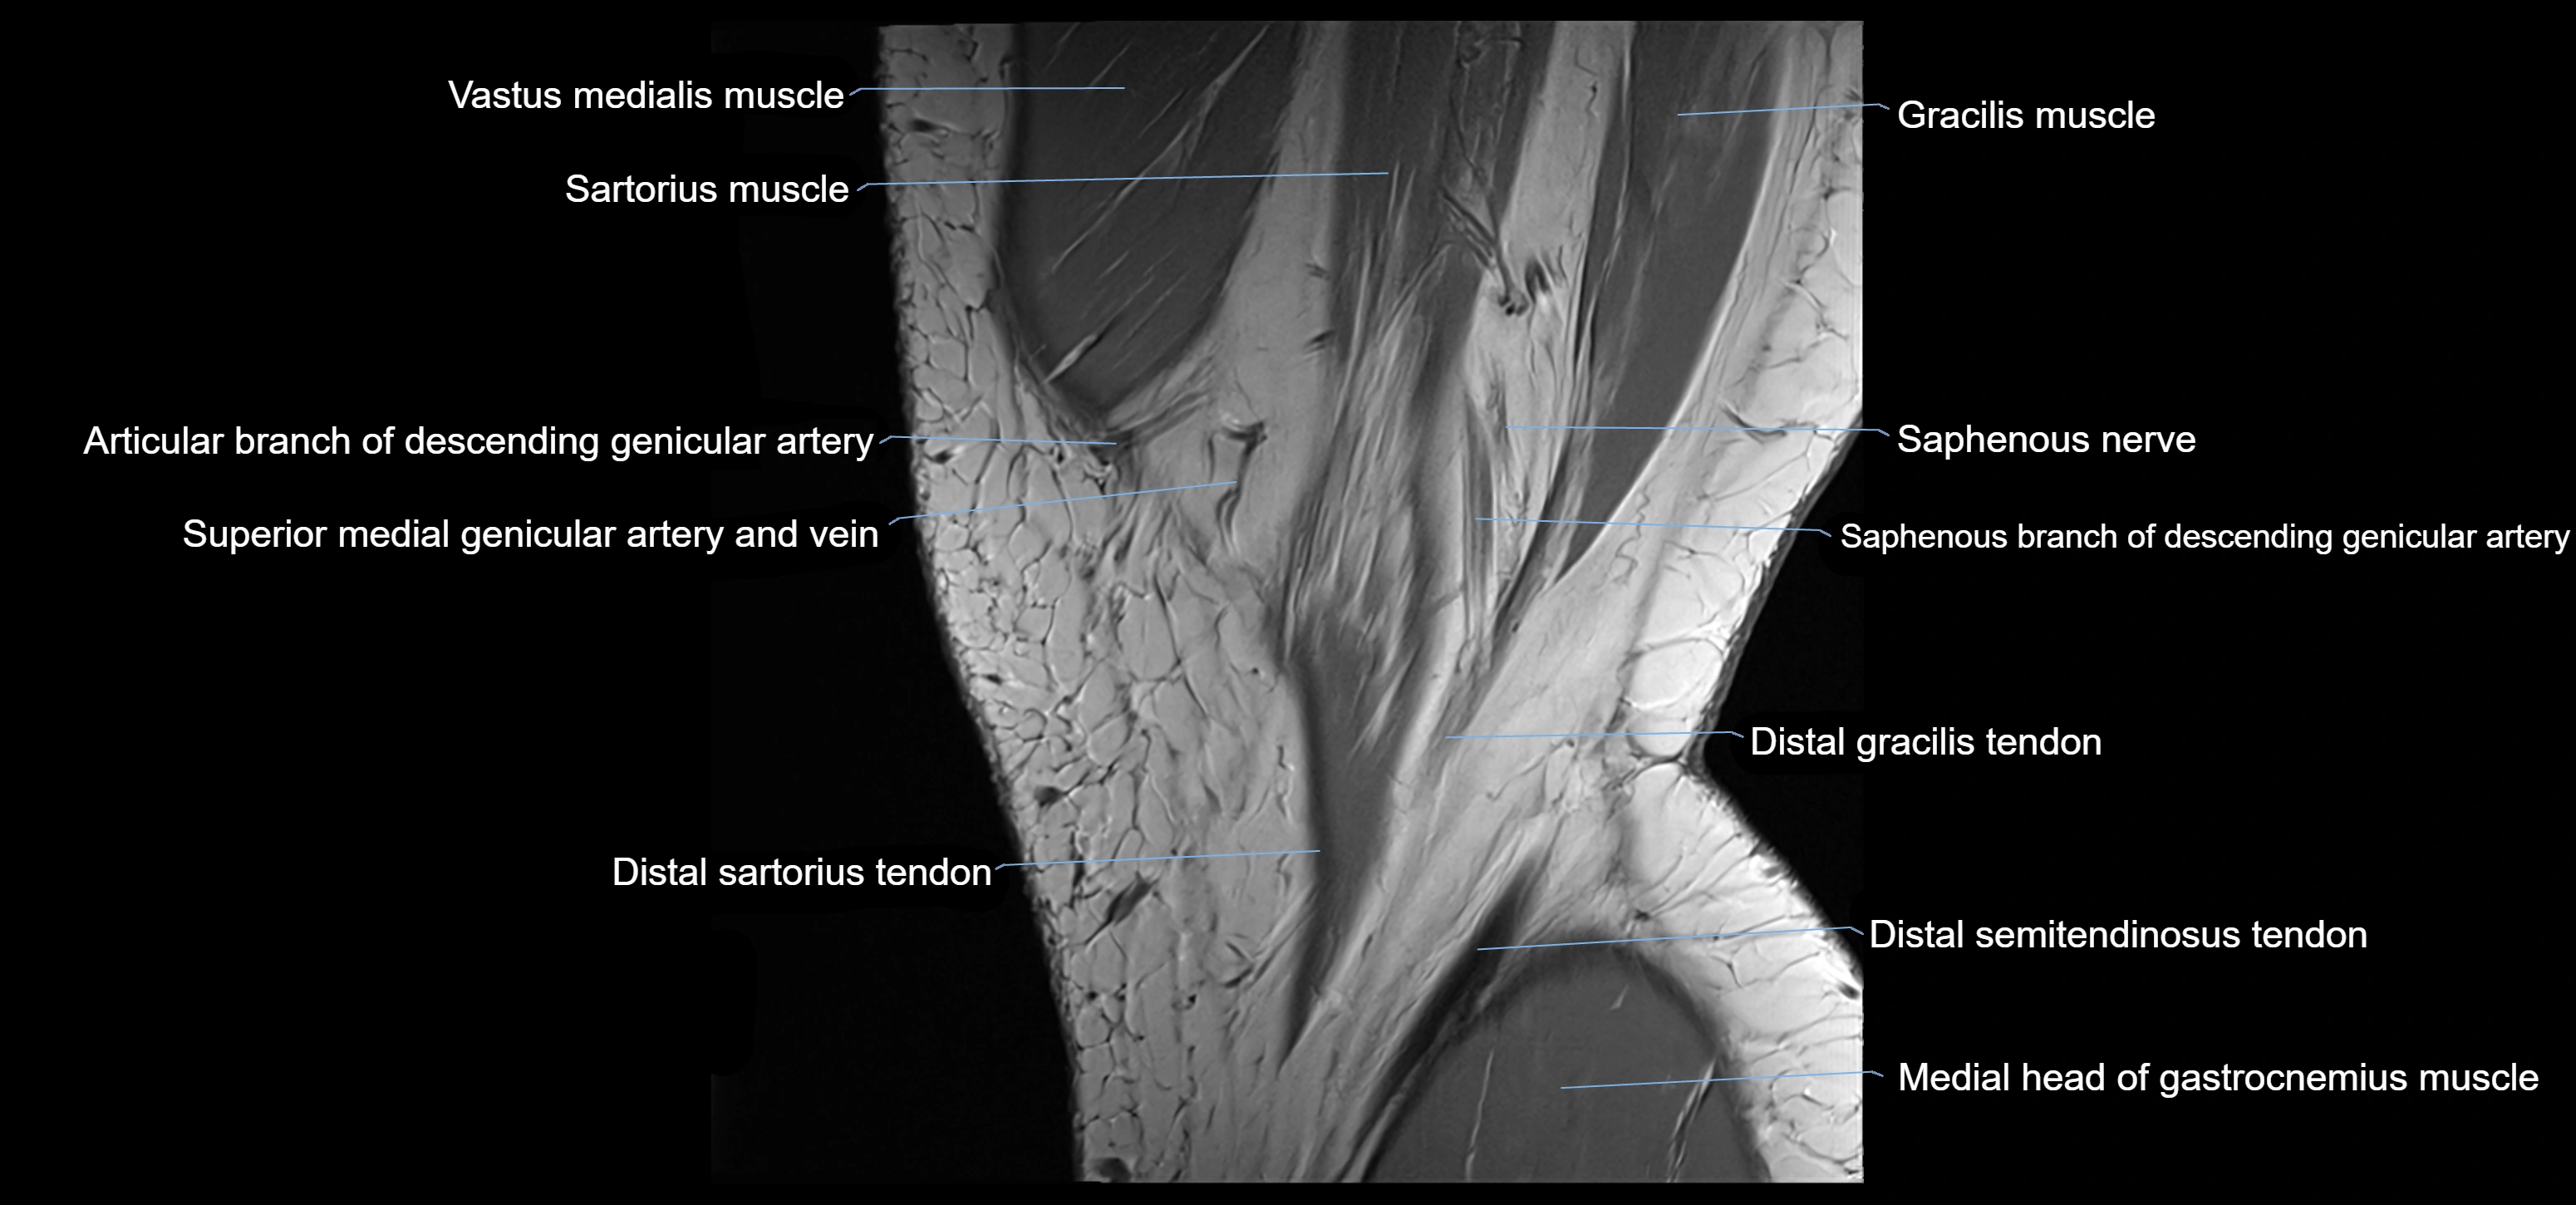

- Descending genicular artery (Articular branches)

- Descending genicular artery (Saphenous branch)

- Gracilis tendon (Distal)

- Saphenous nerve

- Sartorius muscle

- Sartorius tendon (Distal)

- Distal semitendinosus tendon

- Medial head of gastrocnemius muscle

- Superior medial genicular artery